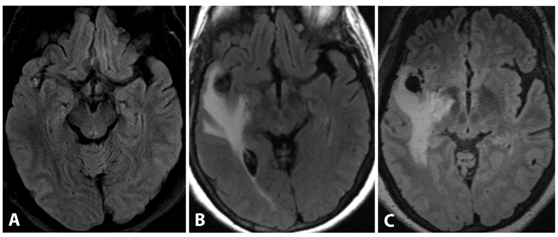

Because the lesion increased in size and was now associated with surrounding vasogenic edema (Figure 3), and there was no evidence of vascular pathology, the primary diagnostic consideration was metastasis. A decision was then made to surgically resect the lesion.

Figure 3 3D T2 FLAIR at 6months from baseline (A) demonstrate worsening vasogenic edema. 3D FLAIR at 1 month post resection (B) demonstrate complete resection of the lesion with resolution of vasogenic edema and minimal residual post-operative blood product.